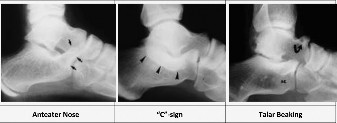

CASE 34 You see a 14-year-old girl in your clinic for the first time who has a …